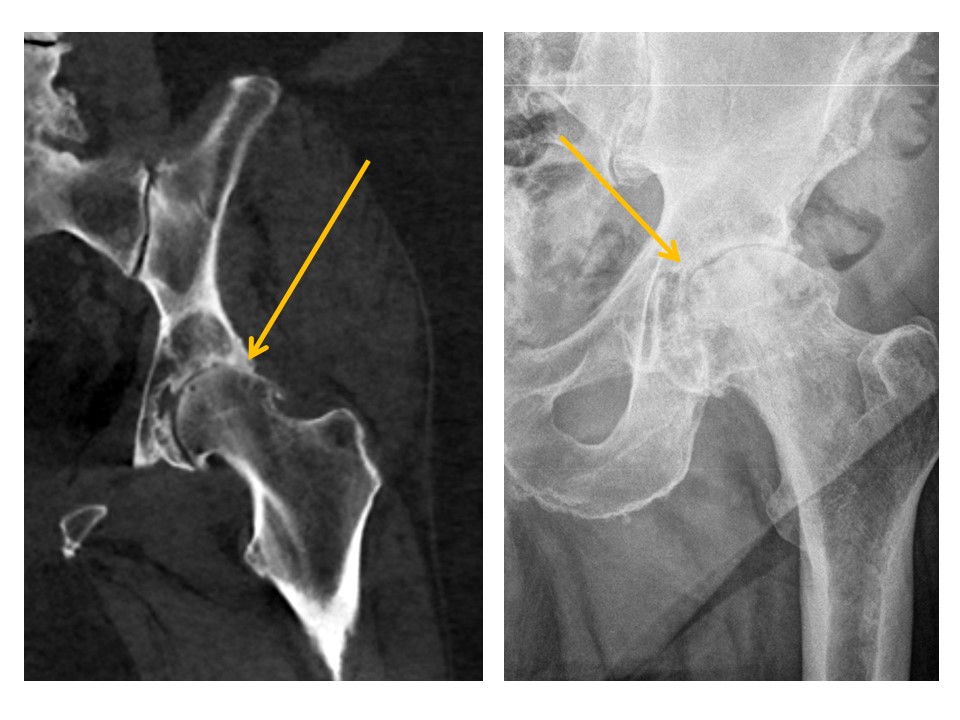

SACRUM and SACROILIAC JOINTS

There are displaced fractures or disrupted/asymmetric foraminal arcs. [Yes/No]

The sacroiliac joints are widened and asymmetric. [Yes/No]

There is malalignment at the inferior margin of the sacroiliac joints. [Yes/No]